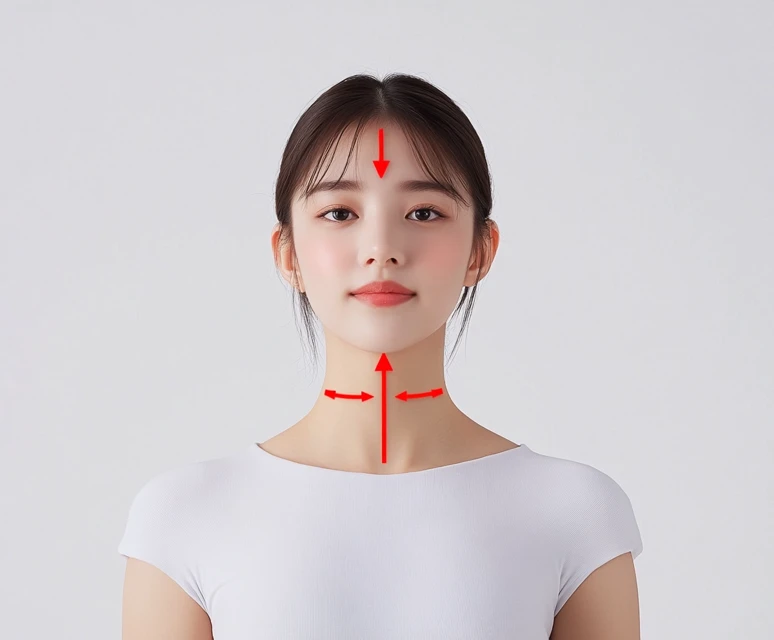

목디스크의 증상은 일반적으로 몇 가지 초기 신호로 나타납니다. 이를 조기에 인지하고 대처하는 것이 매우 중요합니다. 특히 다음과 같은 증상이 나타난다면, 즉시 전문가의 진료를 받는 것이 좋습니다. 목디스크는 주로 목의 디스크가 찢어지거나 탈출되면서 발생하는데, 이로 인해 주변 신경이나 척수에 압박이 가해지는 경우가 많습니다. 주요 초기 신호는 다음과 같습니다:

- 목의 통증: 목디스크의 가장 일반적인 초기 증상은 목의 통증입니다. 이 통증은 지속적일 수도 있고, 특정 자세를 취할 때 더욱 심해질 수 있습니다. 일반적인 근육통과는 다르게, 목의 통증은 종종 뻣뻣함과 함께 오는 경우가 많습니다.

- 머리의 통증: 목디스크의 통증은 두통으로도 이어질 수 있습니다. 특히 긴장성 두통과 비슷한 유형의 두통이 발생할 수 있으며, 이는 경추가 제대로 기능하지 못할 때 나타납니다.